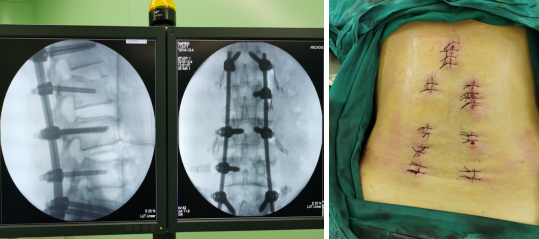

拧入长尾空心螺钉,两侧上连接棒,撑开固定

最终,尚军主任孟磊副主任医师团队在骨科机器人定位下,通过3D图像确定手术中椎弓根螺钉的进钉点、置钉方向以及置钉深度。接着,在机器人系统导航下,机械臂精准移动到置钉位置,医生只在置钉部位切开约1.2cm切口,沿着机械臂所指方向钻入导针,并沿导针置入椎弓根即可,从而使椎弓根螺钉能够以最理想化的方式打入,保证了患者的安全和手术的有效性。

“机器人手术的意义,就是为了减少人手置钉产生的误差,通过精确的定位系统将螺钉精准地置入到最理想的位置,一步到位。因而,机器人手术有着手术精确性更高、安全性更高、术中辐射更少、操作更加稳定等优点。”孟磊副主任医师说,在常规的骨科手术中,医生只能凭借经验及手感,往往还需要借助X光射线在术中透视看到骨头,为了定位准确,患者要反复“吃”射线。一次定位不准还要重新透视再次打螺钉进行调整。